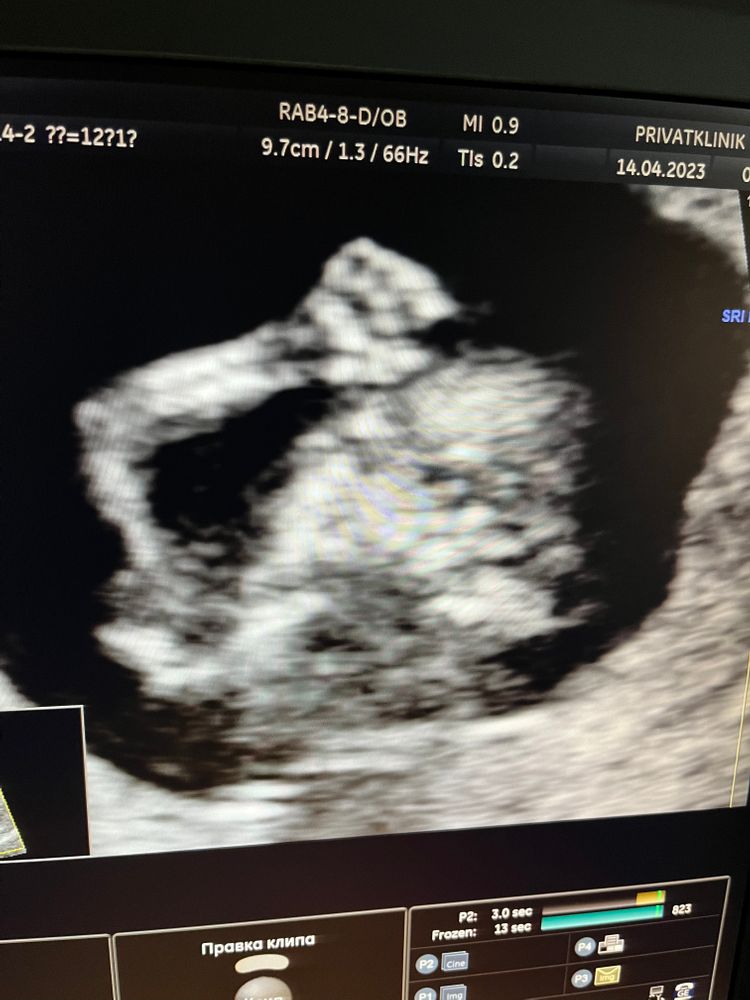

Наш малыш 🤰🎉

Беременность I триместр

Сегодня ходили на 1 скрининг , по результатам все хорошо!!! Теперь ждём анализы крови

Так хорошо уже виден человечек)

14.04.2023